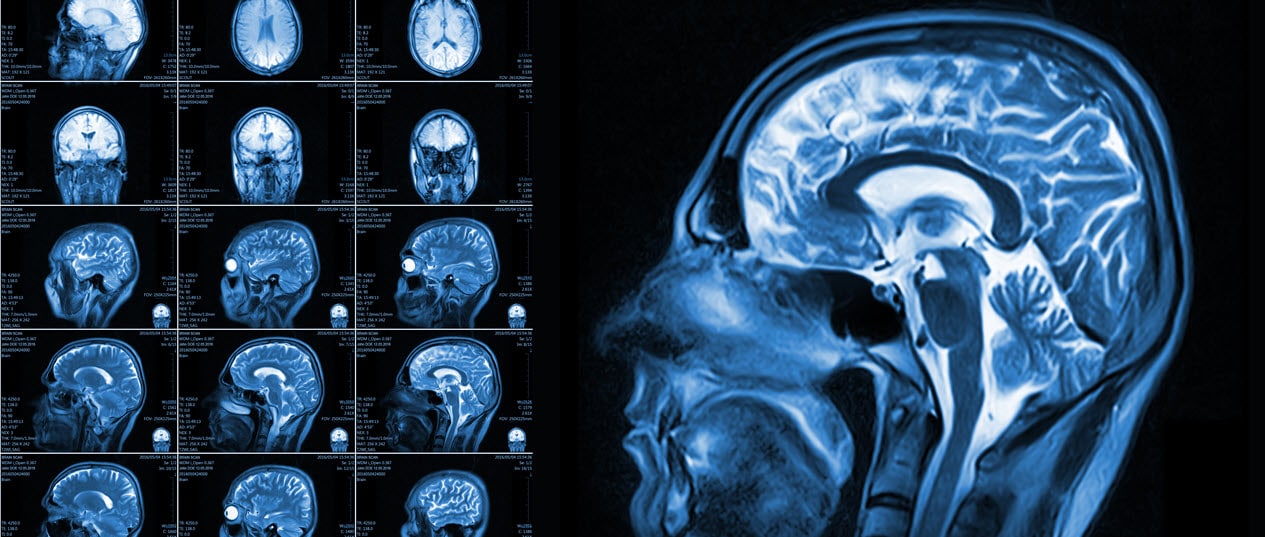

While there are treatment options for victims of TBIs, it is crucial that emergency care is sought. This will be the first treatment and often the most critical in your recovery process. During your emergency room visit, you will likely undergo testing to determine what injuries and the extent of injuries you have sustained.

The Glasgow Coma Scale is used to evaluate brain injuries. The test consists of 15 points that focus on motor skills, verbal questions, eye movements, and more. You will also need to undergo scans such as an MRI and a CT scan. Emergent surgery may be needed in some extreme cases. This type of injury will require several members for your care team including: